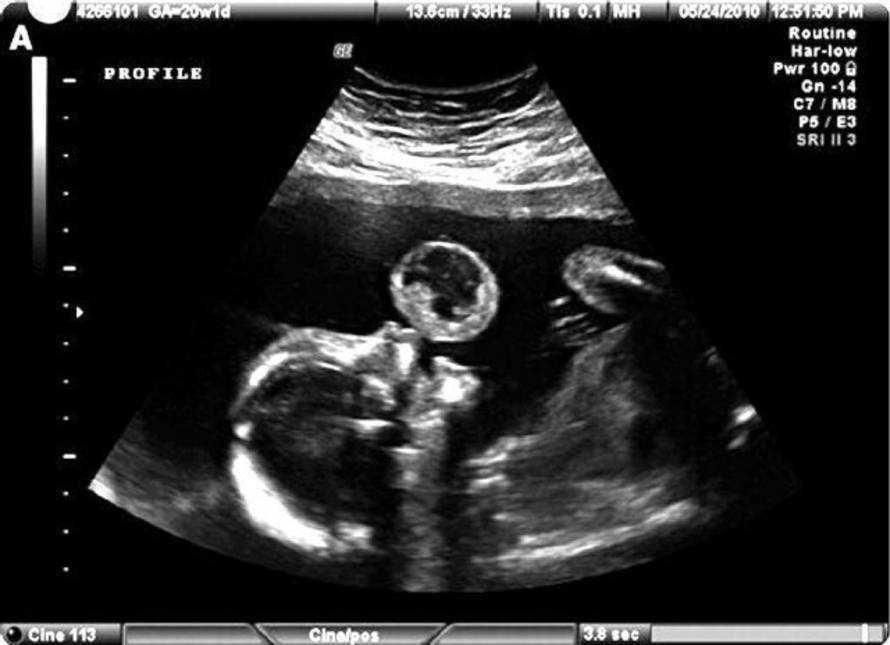

SAD: Liječnici su operirali Tammy kada je bila u 21. tjednu trudnoće. U njezinu maternicu su uvukli iglu i instrumente te odstranili tumor iz usta njezine kćerkice